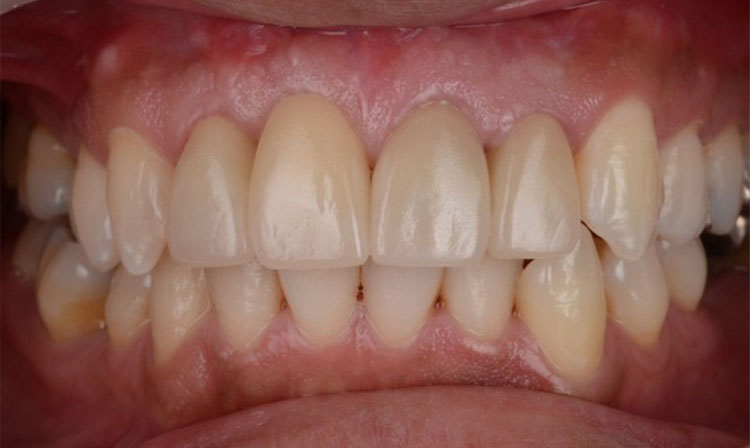

Before

After